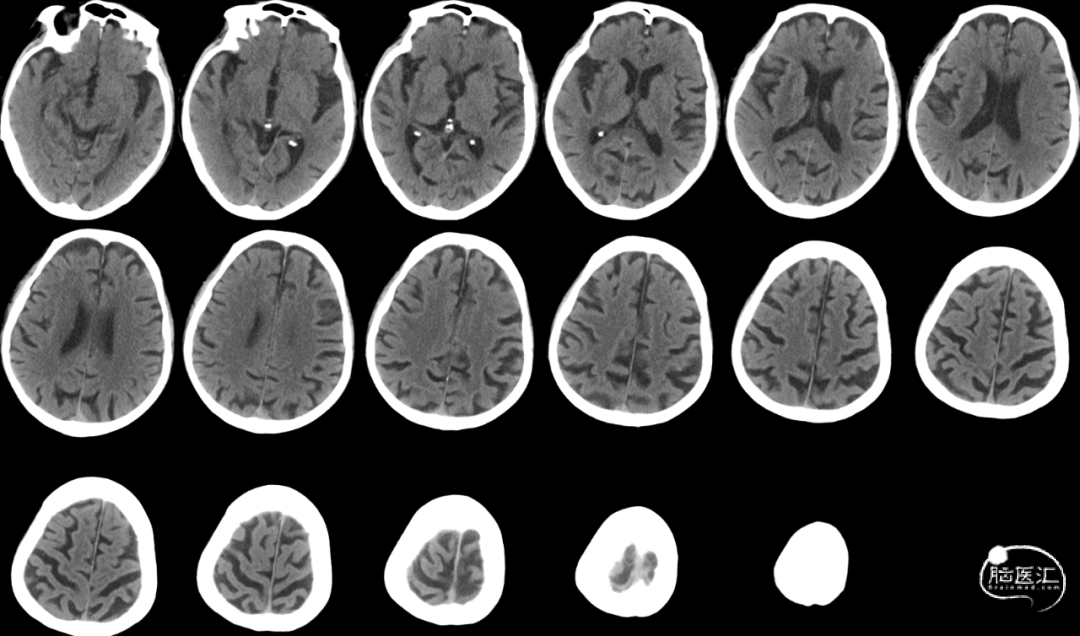

颅脑CT:未见出血,ASPECTS评分 9分。

颅脑CT ASPECTS 9分。

Cranial DWI:右侧壳核、侧脑室旁小片状+皮层点状弥散受限。

Cranial SWI:SVS+AHVs RMCA M1长条血栓。

T2 Flair:丰富的高信号血管征(HVS)。

RICA C1闭塞,来自RACA丰富的软膜支代偿。